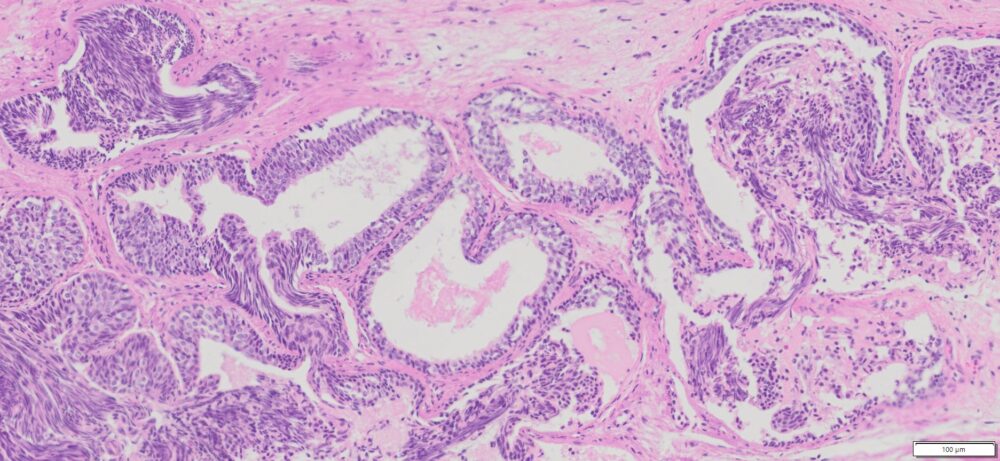

Description

| Tissue | Pathology Diagnosis | Gender/Age (year) | % Tumor area | Tumor Grade | TMN Stage | IHC Data |

| Human Rectum | Moderately differentiated colonic adenocarcinoma with 40% mucinous component | Male/59 | 20% | II | pT4apN1bpMx | NA |

Images for H&E Stain and IHC